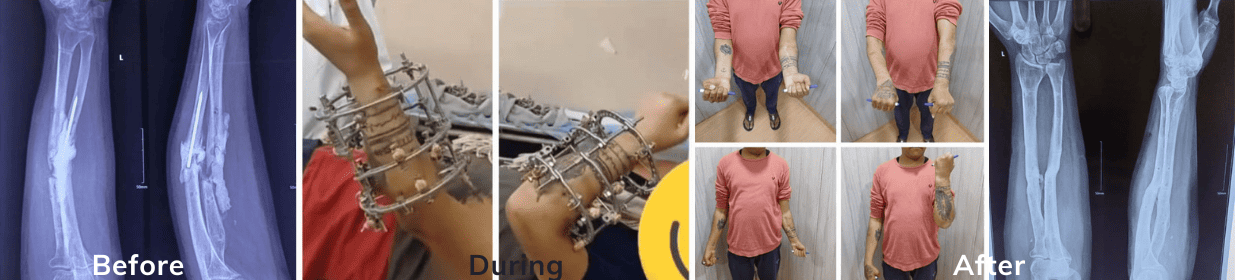

Gap nonunion and failed implant management with Bone Transport

Ilizarov for Upper Limb

Infected nonunion forearm before and after the treatment